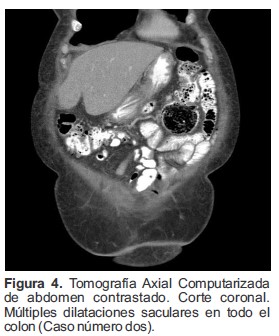

La TAC reportó múltiples imágenes diverticulares en el colon (Figura 4), se observó una imagen, un divertículo gigante del colon localizado hacia la unión del colon transverso con el ángulo esplénico el cual medía 6.0 cm de diámetro y se encontraba opacificado con restos de materia fecal y gas sin mayores signos de sobreinfección (Figura 5).

Figura 4. Tomografía Axial Computarizada de abdomen contrastado. Corte coronal. Múltiples dilataciones saculares en todo el colon (Caso número dos).